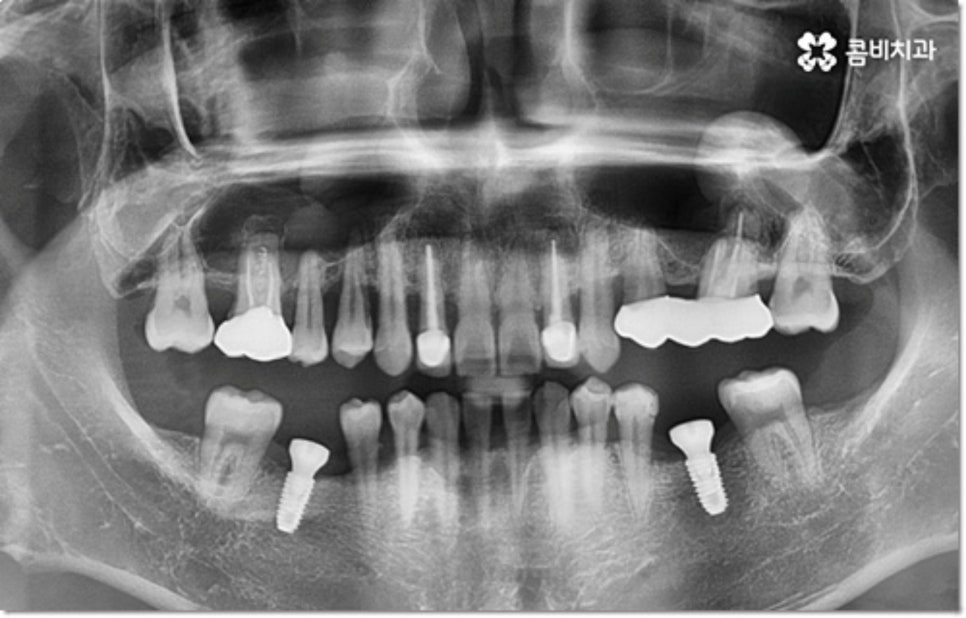

사진에서 볼 수 있는 사례는 아랫니가 크게 부러져서 빠졌을 때 아랫니임플란트 시술을 통해 수복을 해 준 거예요. 이때 빠른 일상 복귀를 원하는 만큼 기간이 얼마나 오래 걸리는가 하는 것은 임플란트 시술을 받으시는 분들의 가장 주된 관심사 중 하나라고 할 수 있는데요.

임플란트 시술 기간은 환자분들의 상황에 따라 달라지는 것이지만 보통 빠르면 36개월, 뼈이식이나 상악동 거상술과 같은 선처치가 필요한 경우 또는 회복 기간이 생각보다 오래 걸리는 경우에는 8개월1년 넘게 까지도 걸릴 수 있습니다. 혹시 모를 부작용으로 재시술을 받게 되는 경우도 있기 때문에 치과를 선택하실 때 말씀드린 의료진의 숙련도 외에도 여러 가지 사항들을 꼼꼼하게 따져보실 필요가 있어요. 3D CT 와 같은 정밀 장비로 환자분들의 잇몸 상황 또는 교합 등을 세밀하게 살펴보고 그에 맞춰 무리하지 않게 임플란트 식립을 진행하는 치과에서 검진부터 사후관리까지 체계적으로 케어받는 것이 중요한 거예요.